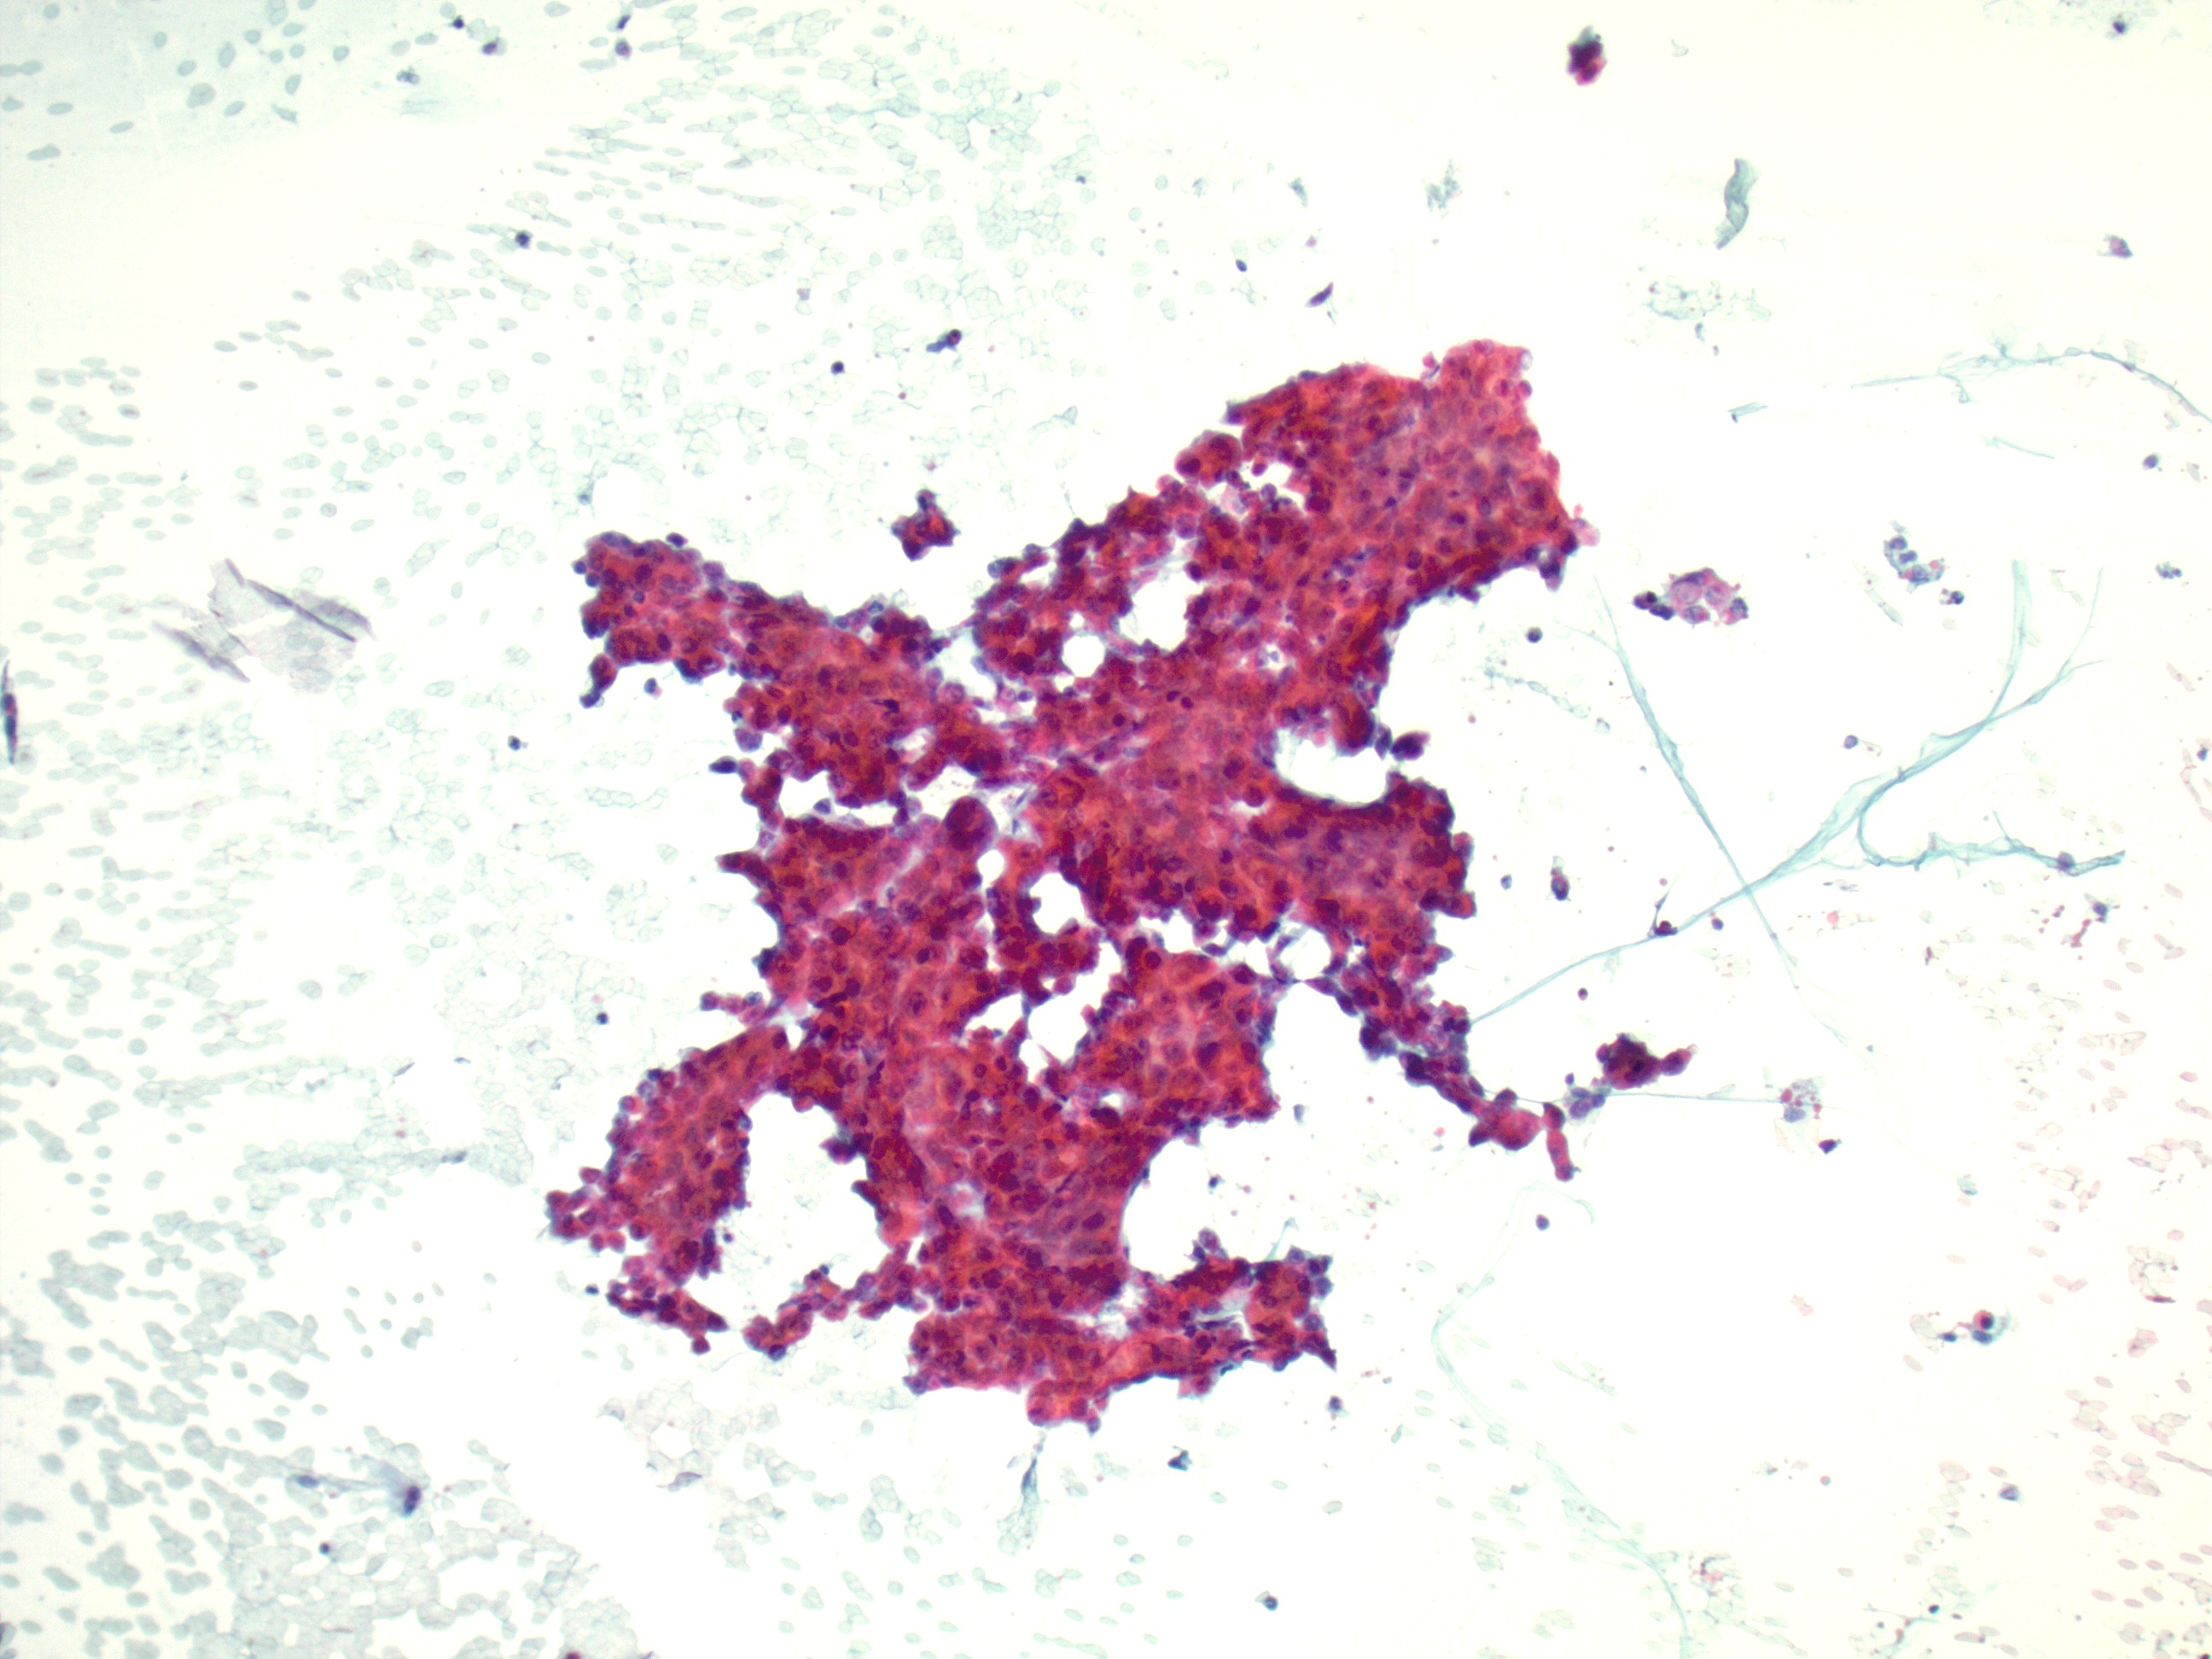

Specimen Type: 11L Lymph node, Traditional smear with Diff-Quik, ThinPrep® Non-Gyn, Cell Block

HCC has 3 main patterns: trabecular, pseudoglandular (acinar), and compact.1 Bile is prominent in some tumors, and cytoplasmic inclusions such as Mallory hyaline bodies, globular hyaline bodies, pale bodies, and ground glass are possible.1 HCC can present in a wide range of appearances, from poorly to well differentiated.1 Well differentiated HCC is highly cellular with an architecture that has isolated cells, naked nuclei, trabeculae surrounded by endothelial cells, pseudoglandular structures, transgressing vessels, and irregularly arranged sheets.1 HCC cells can retain benign hepatocellular criteria including polygonal shape, abundant eosinophilic granular cytoplasm, increased nuclear to cytoplasmic ratios, large round nuclei with prominent nucleoli, intranuclear pseudoinclusions, and intracellular bile1. Poorly differentiated HCC tends to be highly cellular with isolated cells or clusters and has pleomorphism, atypical mitoses, giant cells, spindle cells, bile, and less obvious hepatocytic differentiation.1 HCC cells tend to stain positively for HepPar1, ARG-1, CAM 5.2, and CEA.1 Positive expression of albumin by in-situ hybridization has also been shown to be a robust marker for HCC and can be more sensitive and specific in comparison to ARG-1 and HepPar1.7

In metastatic HCC, the cytologic criteria and immunophenotype are similar to that of primary HCC, however, loss of expression of the traditional immunohistochemical stains can occur.2 Cytologic specimens have an architecture of single tumor cells, trabecular pattern, traversing capillaries, surrounding endothelium, and naked nuclei.2 Cells have cytoplasmic vacuolization, prominent nucleoli, and giant tumor cells.

The cytologic features of this case were tumor cells singly or in groups, prominent nucleoli, granular cytoplasm, traversing capillaries, and some surrounding endothelial cells. The IHC staining of the lymph node biopsy determined that the cells were positive for CAM4.2, glypican-3, and focally positive for arginase while negative for HepPar-1, NKX3.1, TTF-1, and p40. In-situ hybridization for albumin was also positive.